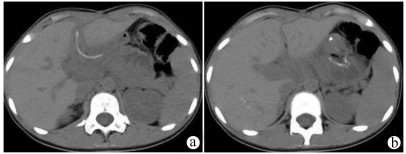

Complete rupture of the pancreas and duodenum caused by car accident in children: A case report

Figures(2)